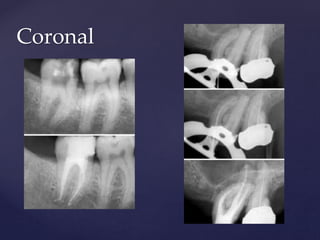

Types according to it’s morphology

1. Apical

2. Middle

3. Coronal

4. Combination

Types according to it’s location

Apical

Coronal

Middle